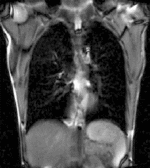

| fixed image/target | moving image |

| |

| unregistered moving series | moving input after registration (only frames 1-27 shown) |